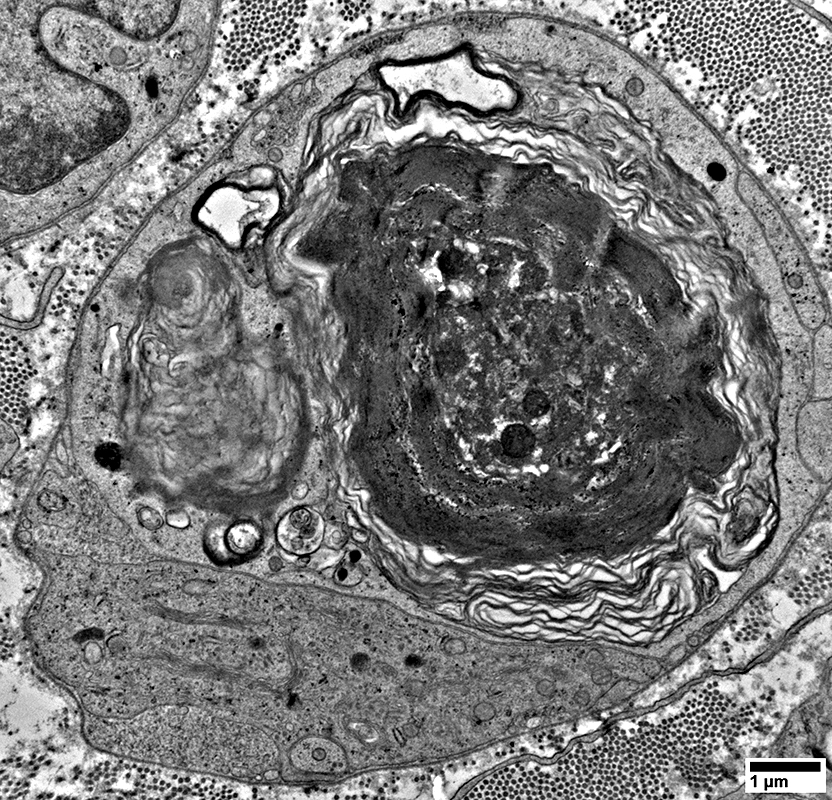

Myelin Damage: Lipid Droplets & Ovoids in Schwann cells

From: R Schmidt